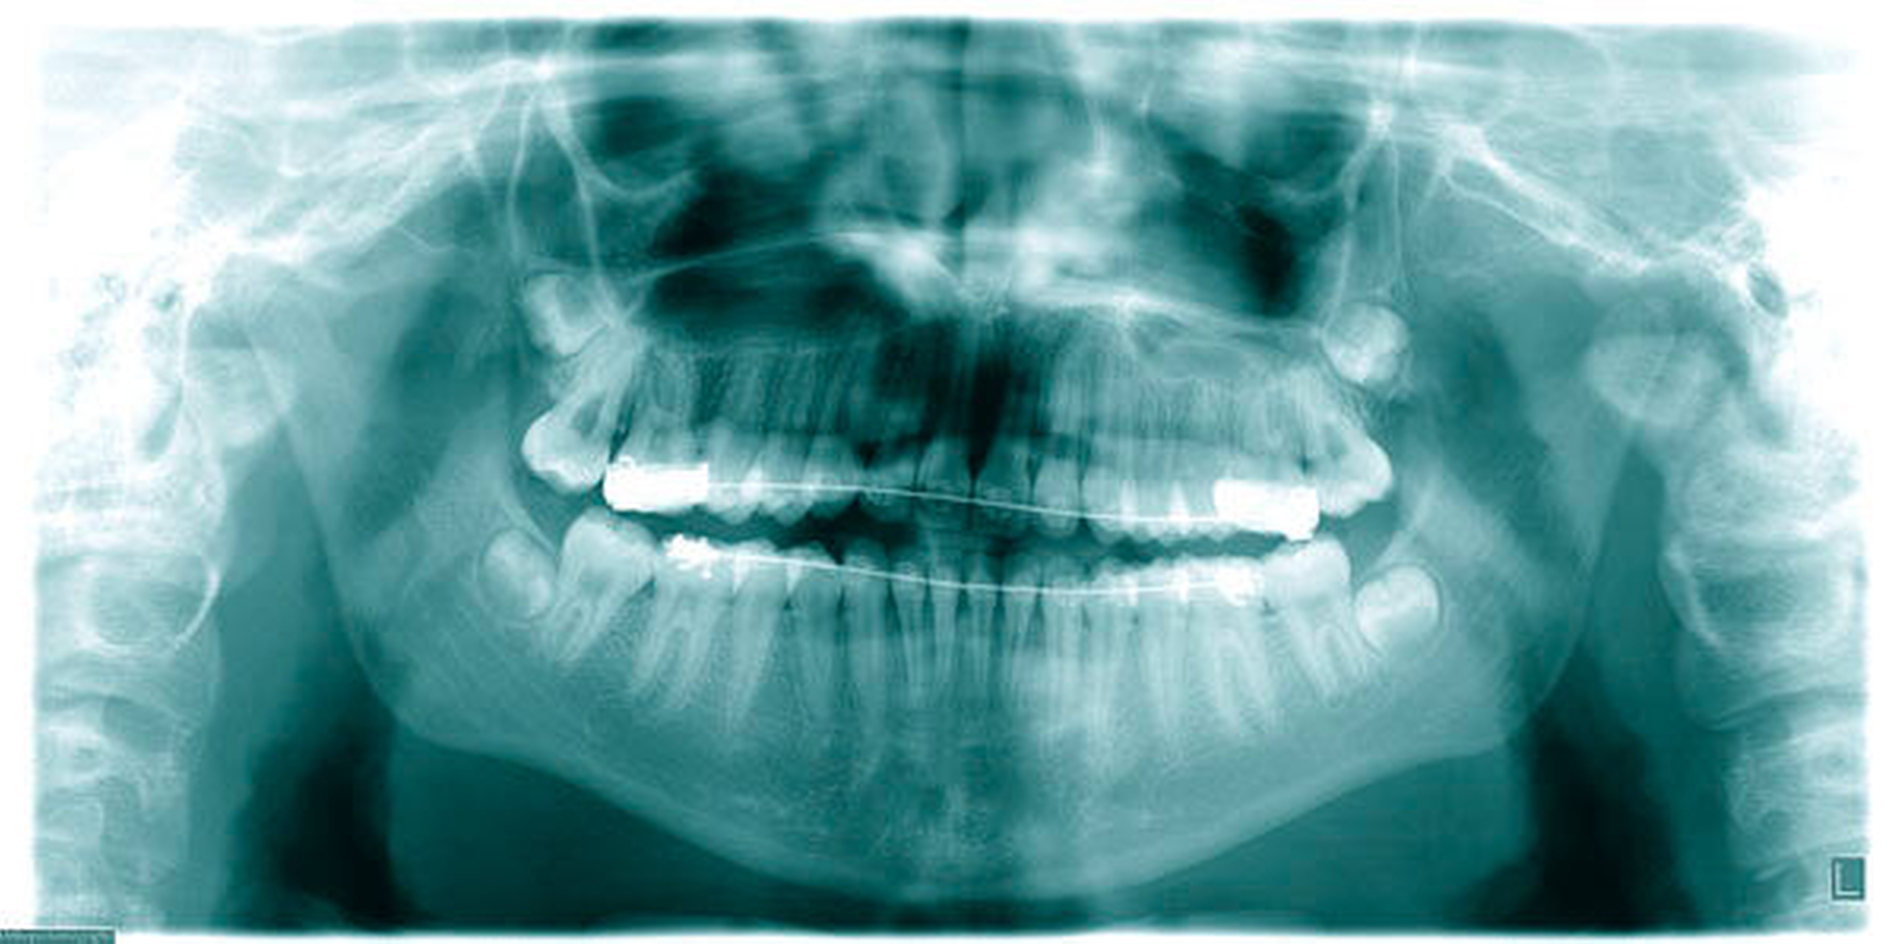

Das Prinzip einer CAD/CAM-gesteuerten Insertion wird anhand einer zehnjährigen Patientin mit einem Platzmangel für die oberen Eckzähne dargestellt (Abbildungen 4a, 4b). Die Behandlung begann mit dem Anpassen von Molarenbändern und einem Silikon-Abdruck des Oberkiefers, der mit dem FRS an das zahntechnische Labor gesendet wurde und dort mit dem FRS der Patientin überlagert wurde. So konnten geeignete Insertionsstellen virtuell geplant werden (Abbildungen 1, 2a, 2b). Nach Rücksprache mit dem Behandler bezüglich der Mini-Implantatpositionen erfolgte die Herstellung der Insertionsschablone (Abbildung 3). Parallel dazu wurde auch der Beneslider [Wilmes, 2010] hergestellt, der zusammen mit der Insertionsschablone geliefert wurde (Abbildung 5). Mithilfe der Insertionsschablone konnten die Mini-Implantate und der Beneslider im selben Termin eingesetzt werden (Abbildungen 6, 7a, 7b). Nach 10 Monaten Distalisierung waren die Molaren in der Zielposition und es war ausreichend Platz für die Eckzähne vorhanden (Abbildungen 8a, 8b), so dass Brackets für die zweite Phase der Behandlung eingesetzt werden konnten. Die Multibracket-Apparatur (Abbildung 9) konnte nach 12 Monaten entfernt werden (Abbildungen 10, 11).